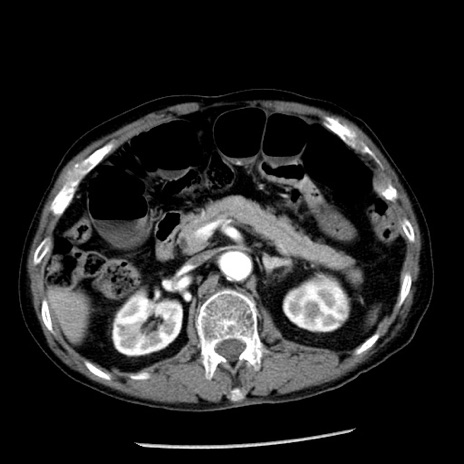

症例26(横断像)

冠状断像

【症例】80歳代男性

【主訴】嘔吐

【現病歴】昨晩2回嘔吐あり、今朝になっても嘔吐あり。来院。

【既往歴】胃潰瘍

【身体所見】意識清明、BT 37.6℃、BP 166/95mmHg、HR 100bpm、SpO2 97%、腹部:平坦・軟、腸蠕動音聴取良好、圧痛なし。

【データ】WBC 21900、CRP 1.46